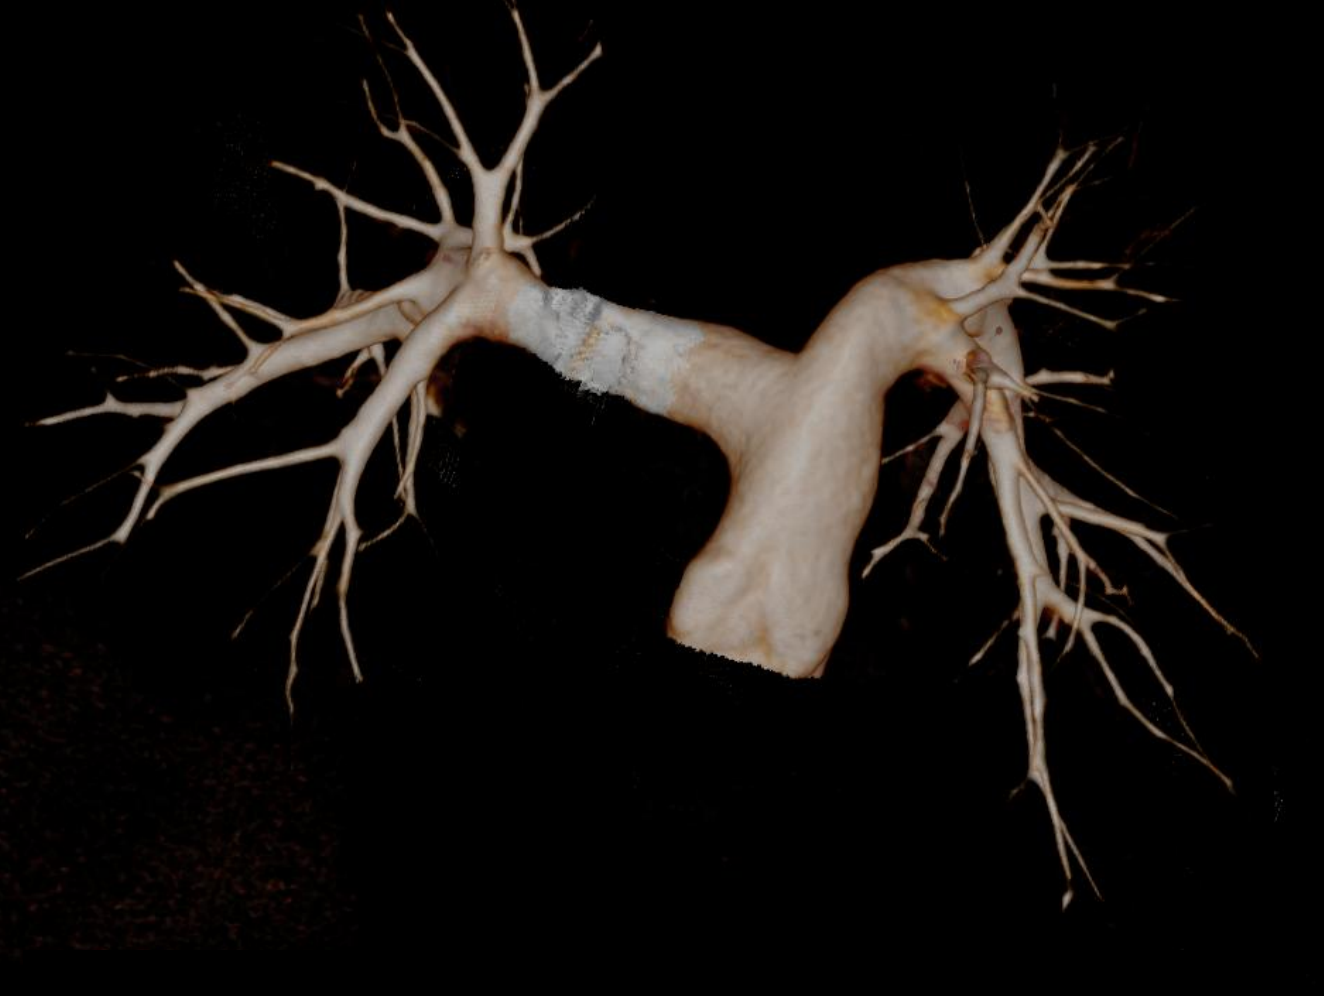

Hệ thống CT tiên tiến này sở hữu tốc độ quay siêu nhanh 0,286 giây, bóng tia X công suất 7,5 MHU (hiệu dụng lên đến 27,1 MHU) cùng detector độ rộng 40 mm. Nhờ các công nghệ hiện đại, hiệu suất chụp tim vượt trội được nâng lên một chuẩn mực mới, mang lại hình ảnh tim mạch chính xác và ổn định. Thiết bị tích hợp nền tảng AI toàn diện, bao phủ toàn bộ quy trình từ định vị bệnh nhân, quét, kiểm soát liều, giảm nhiễu và triệt tiêu artefact đến hậu xử lý hình ảnh và hỗ trợ chẩn đoán, đảm bảo độ chính xác vượt trội ngay cả trong những tình huống lâm sàng phức tạp nhất.